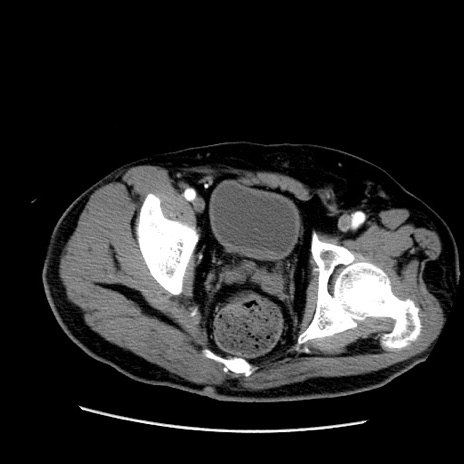

症例22(横断像)

【症例】50歳代男性

【主訴】腹痛

【現病歴】AVMからの被殻出血のため回復期リハ病棟入院中。 本日午後3時頃急に下腹部痛が出現した。

【既往歴】AVM、被殻出血、虫垂炎、高血圧

【身体所見】意識晴明、左半身不全麻痺、会話の理解は良好、36.5°C、腹部:膨隆、全体に板状硬、下腹部正中に圧痛点あり、反跳痛-、筋性防御不明、右下腹部にope scar

【データ】WBC 9400、CRP 0.06